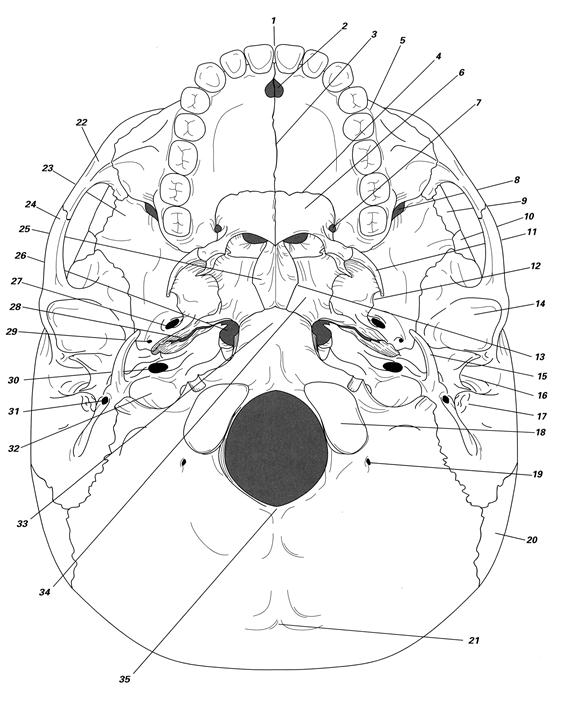

Рис. Наружное основание черепа (по Nielsen/Garbett, 1995):

1 – межрезцовая линия; 2 – резцовый канал; 3 – межмаксилярный шов; 4 – небно-верхнечелюстной шов; 5 – альвеолярное возвышение; 6 – небная кость; 7 – большое небное отверстие; 8 – нижняя глазничная щель; 9 – лобная кость; 10 – теменная кость; 11 – латеральная пластинка крыловидного отростка; 12 – медиальная пластинка крыловидного отростка; 13 – сочленение сошника и клиновидной кости; 14 – височно-нижнечелюстная (гленоидальная) ямка; 15 – шиловидный отросток; 16 – наружный слуховой проход; 17 – сосцевидный отросток; 18 – затылочный мыщелок; 19 - мыщелковый канал; 20 – теменная кость; 21 – инион; 22 – скуловая кость; 23 – большое крыло клиновидной кости; 24 – скуловой отросток височной кости; 25 – крыло сошника; 26 – рваное отверстие; 27 – овальное отверстие; 28 – нижняя каменистая борозда; 29 – остистое отверстие; 30 – каротидный канал; 31 – канал лицевого нерва; 32 – выход внутренней яремной вены; 33 – базион; 34 – тело клиновидной кости; 35 – опистион.